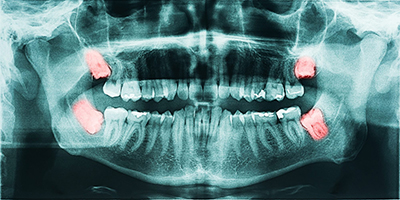

Even if wisdom teeth are not currently painful, they can still cause serious problems beneath the surface. Many issues develop silently and are only detected through proper evaluation and imaging.

Fluid-filled cysts can form around impacted wisdom teeth, gradually damaging surrounding bone and potentially affecting adjacent teeth.

Impacted wisdom teeth can contribute to decay, root resorption, or bone loss in the neighboring second molars.

1Smile Dental uses 3D CBCT imaging to evaluate wisdom teeth with precision. This allows us to: